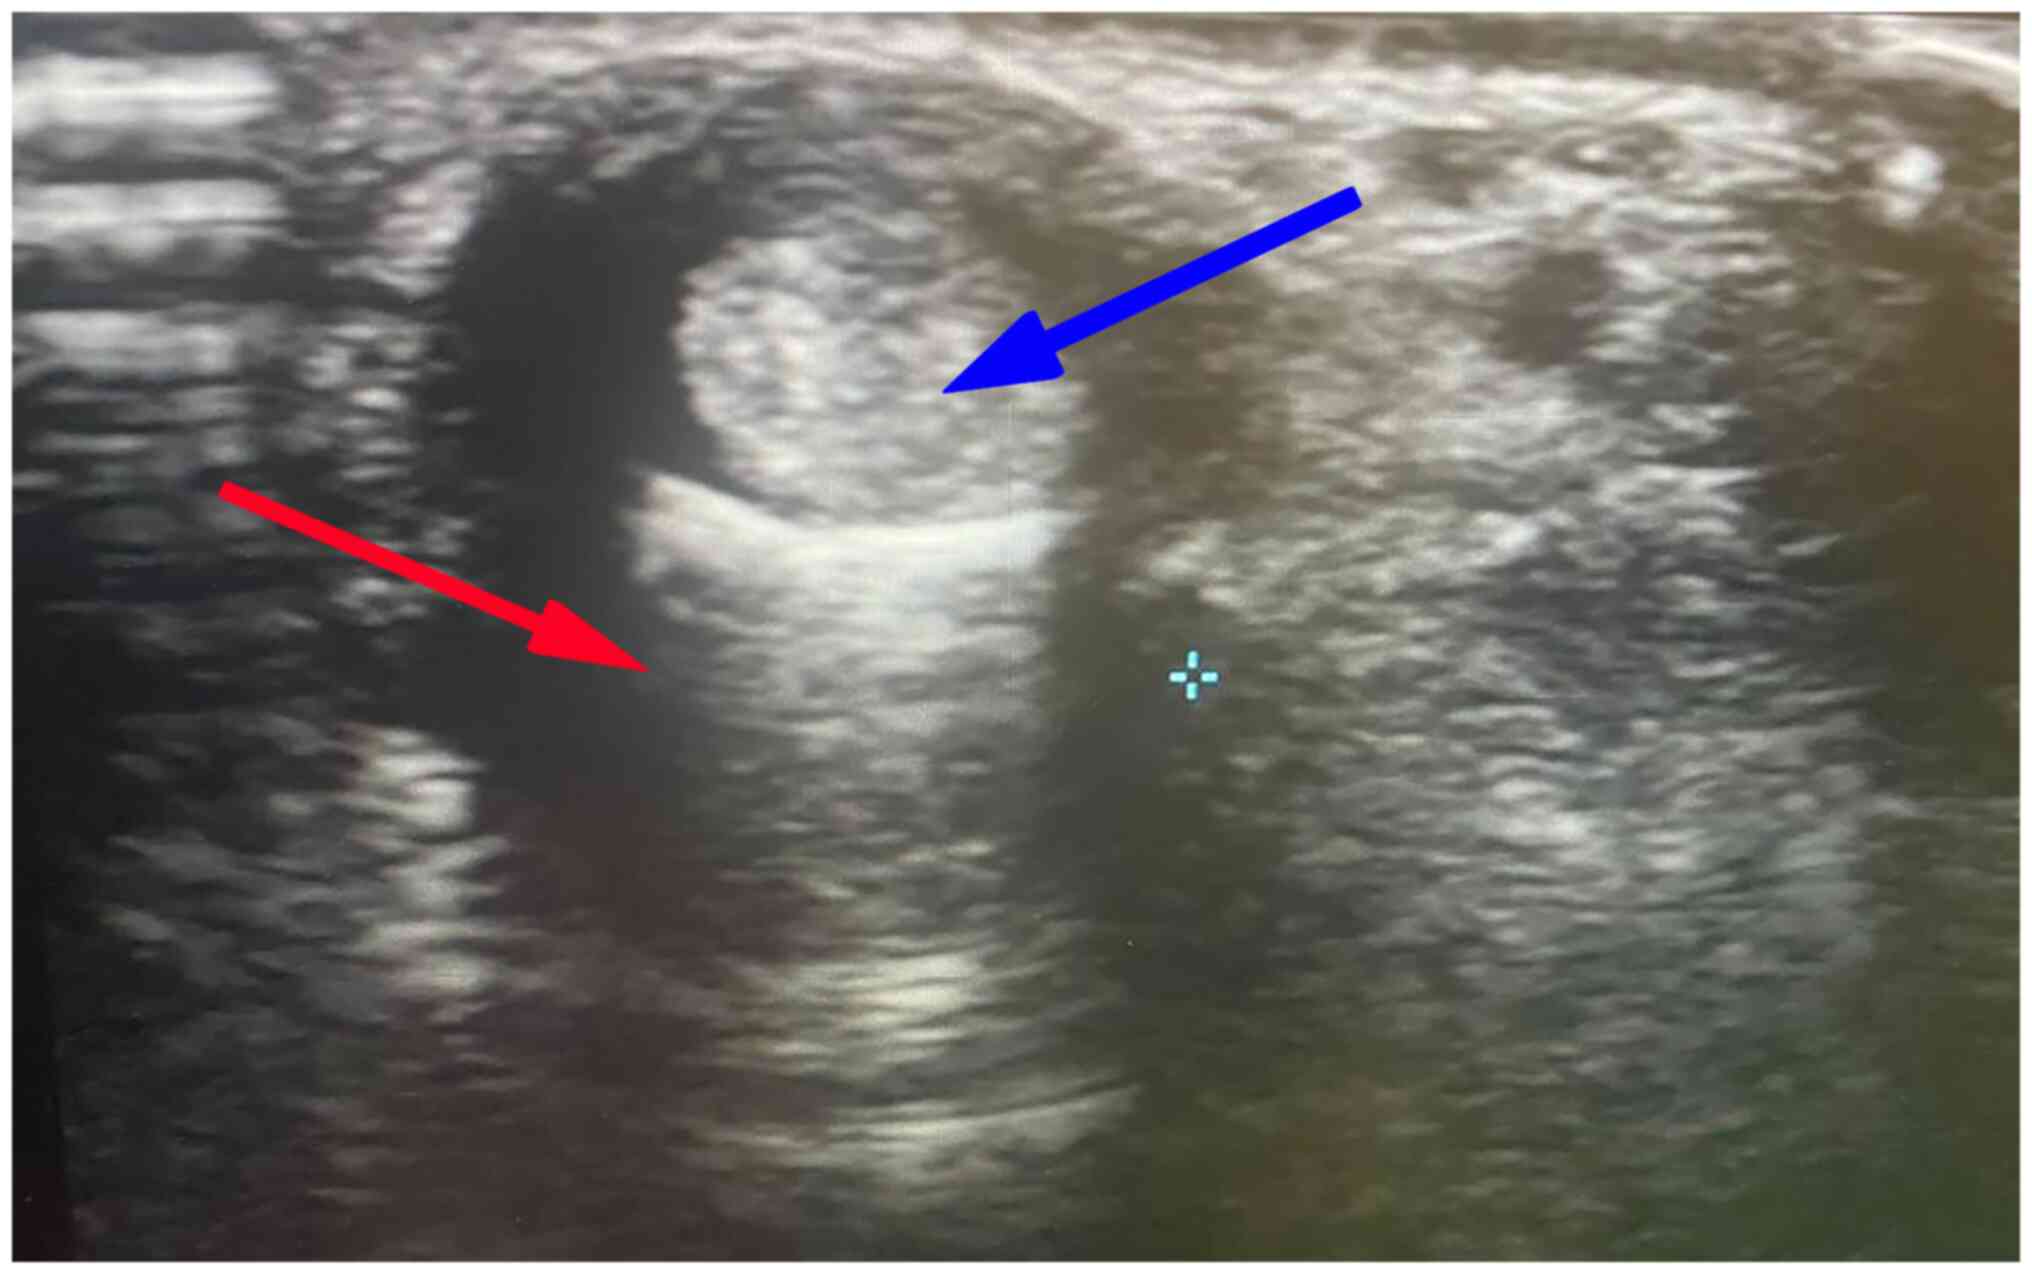

Baseline sonographic findings (as presented in Table III) revealed a thickened retinaculum (1.89±0.5; ranging from 1.3-3 mm) and tendon sheath effusion (2.07±0.52) in all patients (illustrated in Figs. 1 and 2). As regards anatomical variations, 5 patients (41.7%) had septum between APL and EPB, and 4 patients (33.3%) had accessory tendon slips (example illustrated in Fig. 1). However, post-PRP injection, a US examination at the 1- and 3-month follow-up periods revealed a significant improvement in the patients. The thickness of the extensor retinaculum had progressively decreased, from a mean of 1.89 mm pre-injection to a mean of 1.3 mm and 0.96 mm at the 1- and 3-month follow-up, respectively (P<0.001). The tendon sheath effusion observed in all the patients had a mean thickness of 2.07 mm pre-injection. At the 1-month follow-up, effusion was observed in 11 cases (91%) with a mean thickness of 1.6 mm, and at the 3-month follow-up, only 7 of the cases had effusion (58%) with a mean thickness of 0.73 mm (P<0.001). Peri-tendinous hyperemia was initially observed in 7 patients (58.33%), and after the PRP injection this was only observed in 2 patients (16.7%) at the 1-month follow-up (P<0.063) and in no patients (0%) (P<0.001) at the 3-month follow-up (Table III; examples illustrated in Fig. 3). Sonographic improvements observed in two different patients are illustrated in Figs. 4 and 5.

Figure 1

Transverse scan of the first dorsal compartment showing thickened retinaculum (red arrow), with tendon sheath effusion (blue arrow).